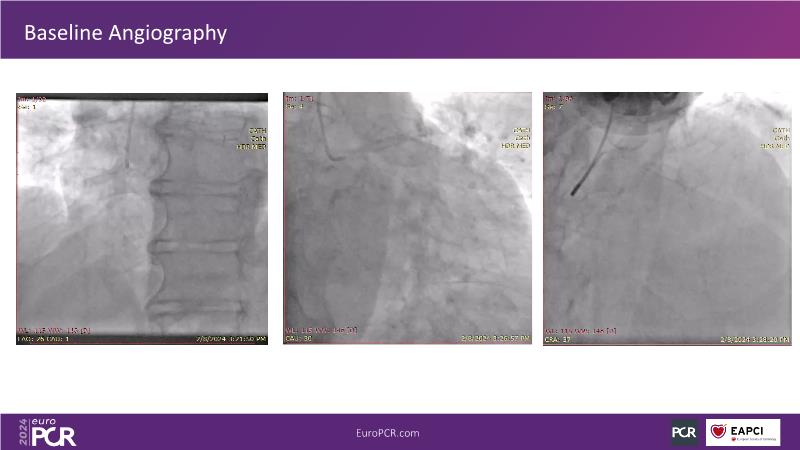

Tune in to this session for insights on optimizing vascular access and closure techniques. Explore steps like thorough CT analysis, ultrasound-guided puncture, and contingency plans for alternative access methods to minimize complications. Discover a novel patch-based closure approach offering immediate hemostasis and simplified usage, addressing issues like re-access associated with other closure technologies. Witness the effectiveness of combining suture- and plug-based closure methods for achieving excellent outcomes.